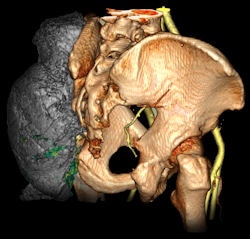

Enterprise-wide 3D aids in decisive surgical calls More radiologists and referring physicians may be pursuing enterprise-wide 3D visualization capabilities, but their preference for such advanced technology isn't just about having the coolest tools in their clinical arsenal. It's about surgical outcomes with the patient as top priority. For example, a surgeon at Illinois Masonic Medical Center in Chicago used 3D tools from Vital Images to visualize a large sarcoma on a patient's hip, recalled Ghanbari. As a result, the surgeon was able to visualize the internal iliac artery in relation to the tumor, which provided him with the confidence to proceed with the surgery, and the 3D views of the muscles and tumor margins determined the strategy for the resection, Ghanbari said. In another case, 3D may have saved a patient's life, according to Moore. A patient who had six toes on one foot was having surgery to remove the extra toe, he said. "Normally the outside toe would be removed. As the patient entered the surgical suite, the surgeon looked at the imaging study in vessel-tracking mode," Moore said. "He could see that a large artery was wrapped around the outside toe. That artery posed a major surgical risk, so an inner toe was removed instead." |

![]() |

| Many enterprise-wide 3D proponents believe the technology can facilitate collaboration between radiologists and referring physicians. Image courtesy of Vital Images. |